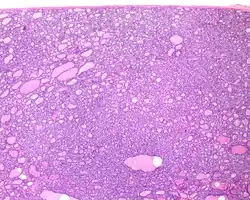

1) Encapsulated or partially encapsulated. The tumors are usually very well delimited or circumscribed, with the majority encapsulated, surrounded by a well formed fibrous connective tissue capsule.

3) Predominantly follicular pattern of growth. Papillary structures should not be present. Further, solid, insular, or trabecular architecture must be <30% of the overall tumor for this category to still apply. Colloid (the material that thyroid follicular cells create) is easily identified throughout.

- ^ Image by Mikael Häggström, MD. Reference for findings: Rachel Jug, M.B.B.Ch., B.A.O., David Poller, M.D., Xiaoyin "Sara" Jiang, M.D. "NIFTP". Pathology Outlines.